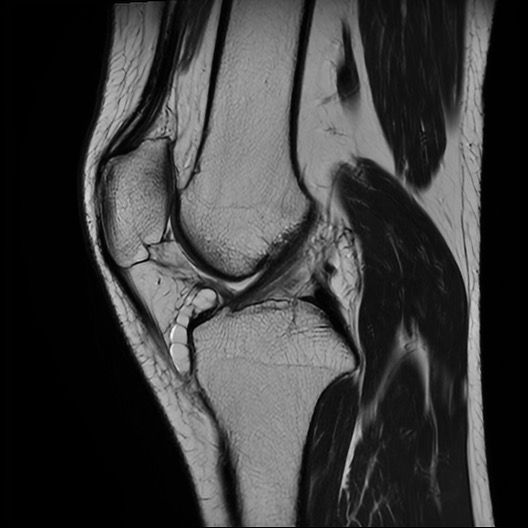

글개건하에 보이는 것은부종이나 혈종, 점액낭염일 수 있고 프롤로 주사 후 일시적인 변화일 가능성이 있어요 MRI에서 슬개건의 두께 변화나 고신호가 보이면 슬개건염 소견에 해당하고 정밀 판독 전까진 예단하기 어렵습니다!

첫번째 두번째 사진은 슬개건하부에 염증으로 보이며

잼액낭의 변성일수도 있겠습니다.

세번째 사진은 무릎 중심부에 십자인대에도 염증 반응을 보이고 있는 것 같습니다.

슬개건 아래에 빈 공간은 염증에 의해서도 발생할 수 있는데요, 정확한 소견은 mri 판독결과가 나온 이후에 확인하는 것이 좋습니다.

일반적으로 슬개건염(Patellar tendinitis)은 슬개골 아래쪽, 즉 슬개건 부위에 건의 부종, 신호강도 증가(염증), 미세 파열 등이 MRI에서 보이는 특징입니다. 특히 T2 강조 영상에서 슬개건 내 고신호(밝게 보이는 부분)가 나타나면 염증성 변화로 해석될 수 있습니다. 만약 이런 신호가 크지 않거나 경계가 뚜렷하지 않다면 경미한 슬개건염일 수 있으며, 보존적 치료(물리치료, 스트레칭, 소염제 등)로도 충분히 회복될 수 있죠

슬개건 하방(아래쪽)에 무언가가 있다는 표현은 몇 가지 가능성을 시사합니다. 대표적으로는 슬개하 지방체(호파 패드)의 염증이나 부종이 해당 부위에서 흔히 발견됩니다. 이는 점액낭염처럼 보일 수도 있고, 운동 후 반복적인 압박이나 마찰로 생기기도 해요. 혹은 점액낭(버사)이 부어있거나, 아주 드물게 결절성 병변, 낭종, 또는 혈종 등이 있을 수도 있습니다. 초음파나 MRI 판독 결과에서 "fluid collection(액체 고임)" 또는 "edema(부종)"이라고 나오면 비교적 경미한 문제일 가능성이 높습니다.